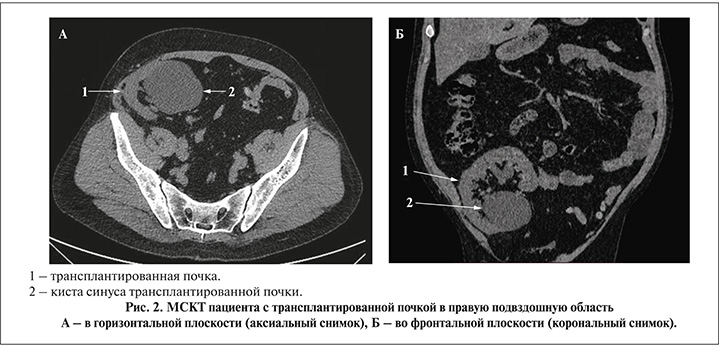

Кисты трансплантированной почки зафиксированы у щести пациентов. Размер кист варьировался от 1 до 6 см, двум пациентам потребовалось оперативное вмешательство. Необходимость вмешательства определялась наличием клинических проявлений в виде формирования нарушения уродинамики, связанного с расположением кисты в проекции почечного синуса. Обоим пациентам выполнено чрескожное дренирование кисты, у одного через 2 года диагностировано рецидивное течение (рис. 2).

Наличие рецидивного кистозного образования трансплантированной почки с нарастанием дисфункции органа стало определяющим для выполнения лапароскопического иссечения кисты. Интраоперационно с целью минимизации операционной травмы при диссекции тканей был использован лапароскопический ультразвуковой датчик.

Послеоперационный период протекал без осложнений, отмечено улучшение функции трансплантата в виде снижения креатинина с 164 до 137 мкмоль/л. Признаков рецидива кисты за период наблюдения 6 мес. нет. Морфологическое заключение удаленного образования расценено как простая киста почки.